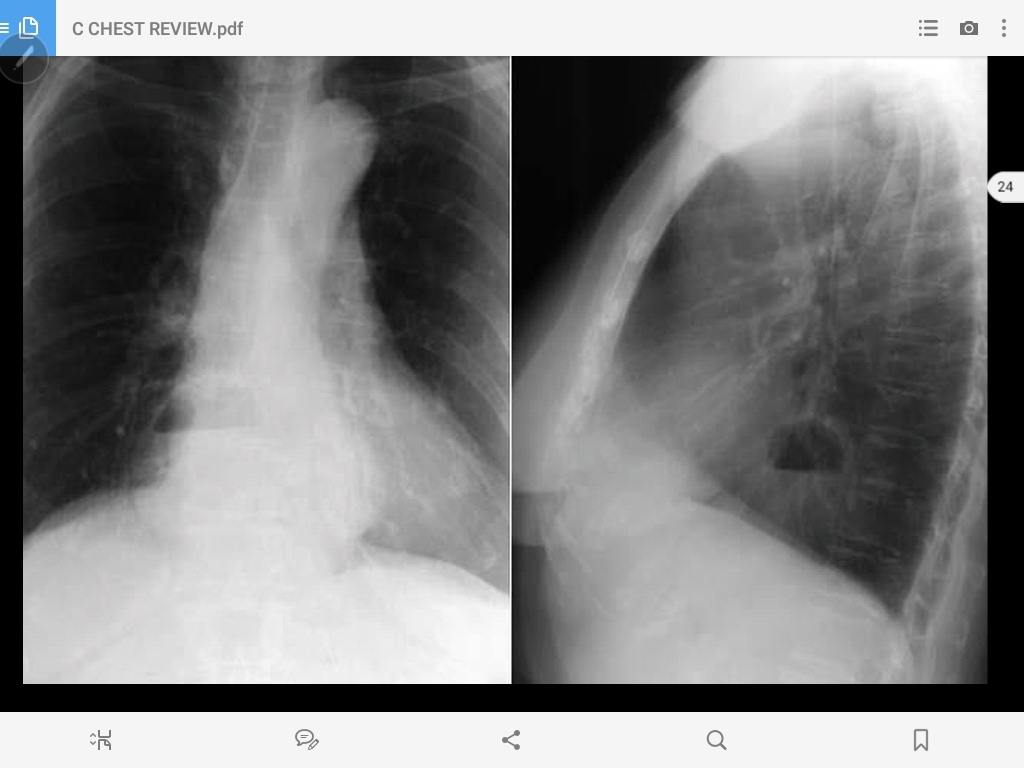

pectus excavatum